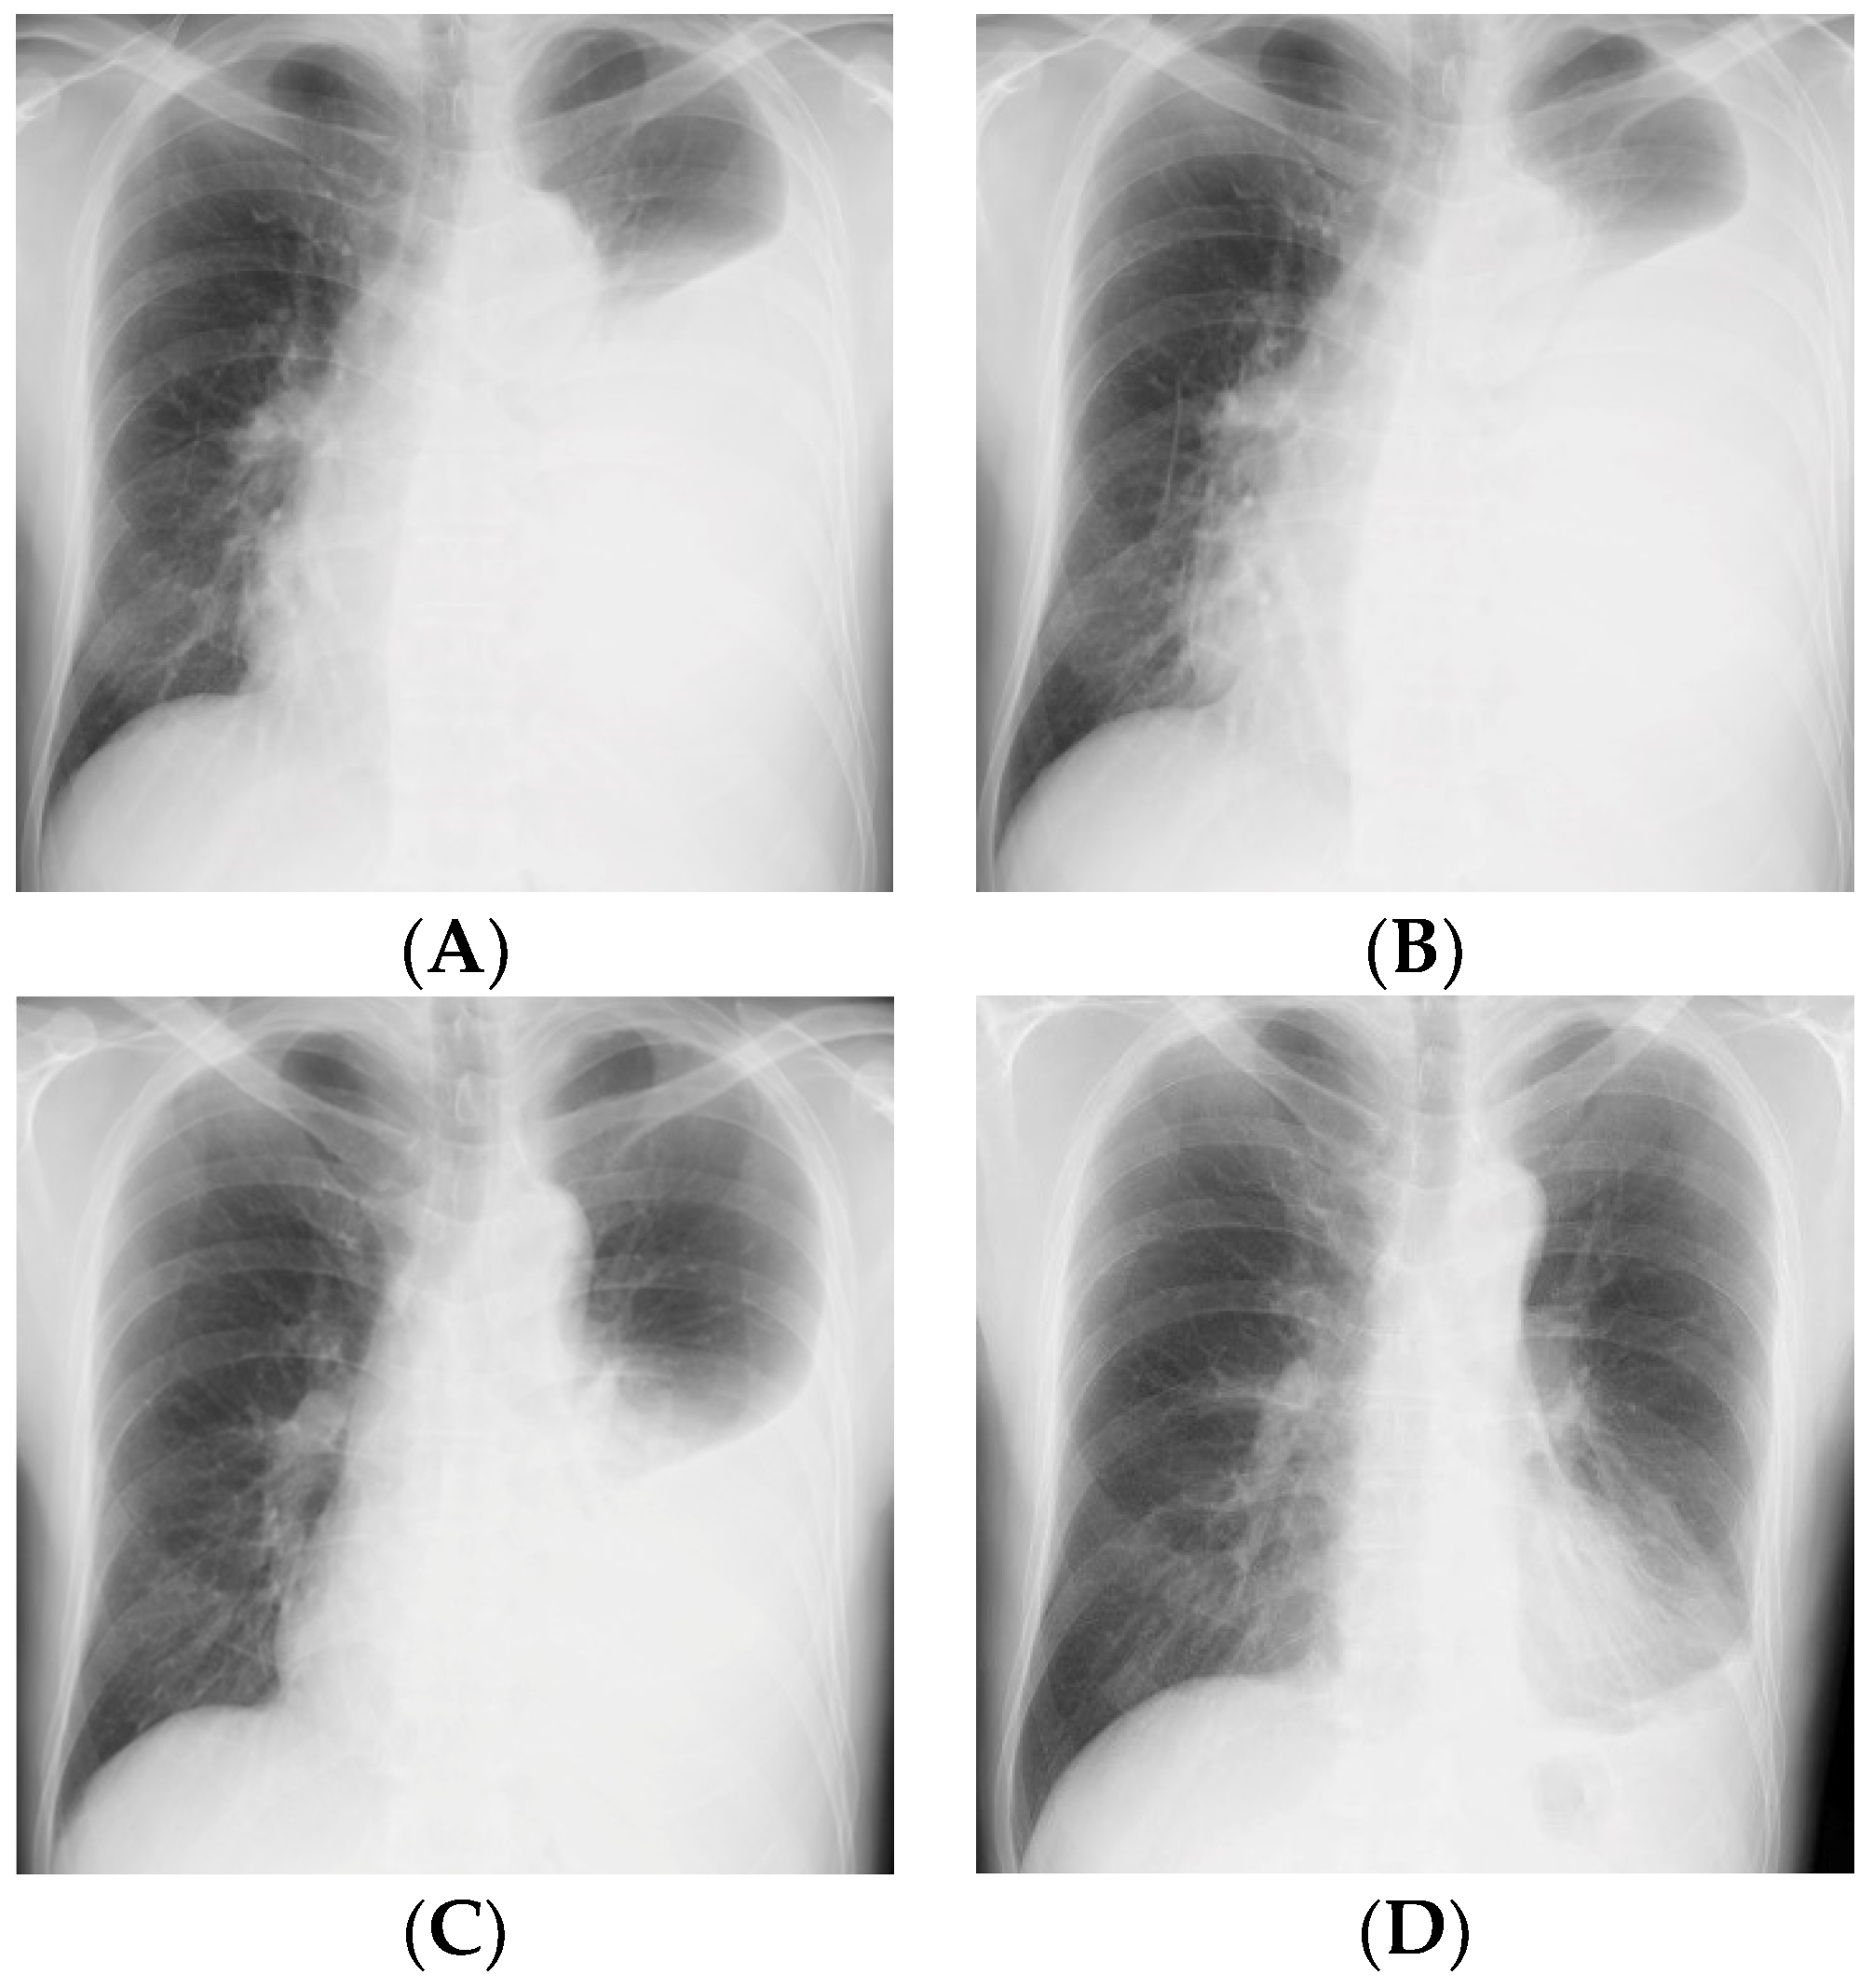

2. Case Presentation Section